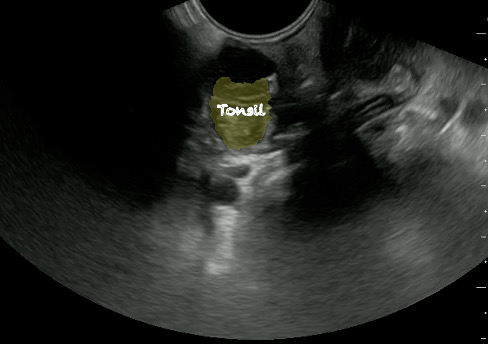

- Normal Tonsil

- The ovoid tonsils appear striated with hyperechoic bands and hypoechoic parenchyma, as well as lobulated margins.

- Figure 42 and 43. Normal Tonsil

Video 25. Normal tonsil